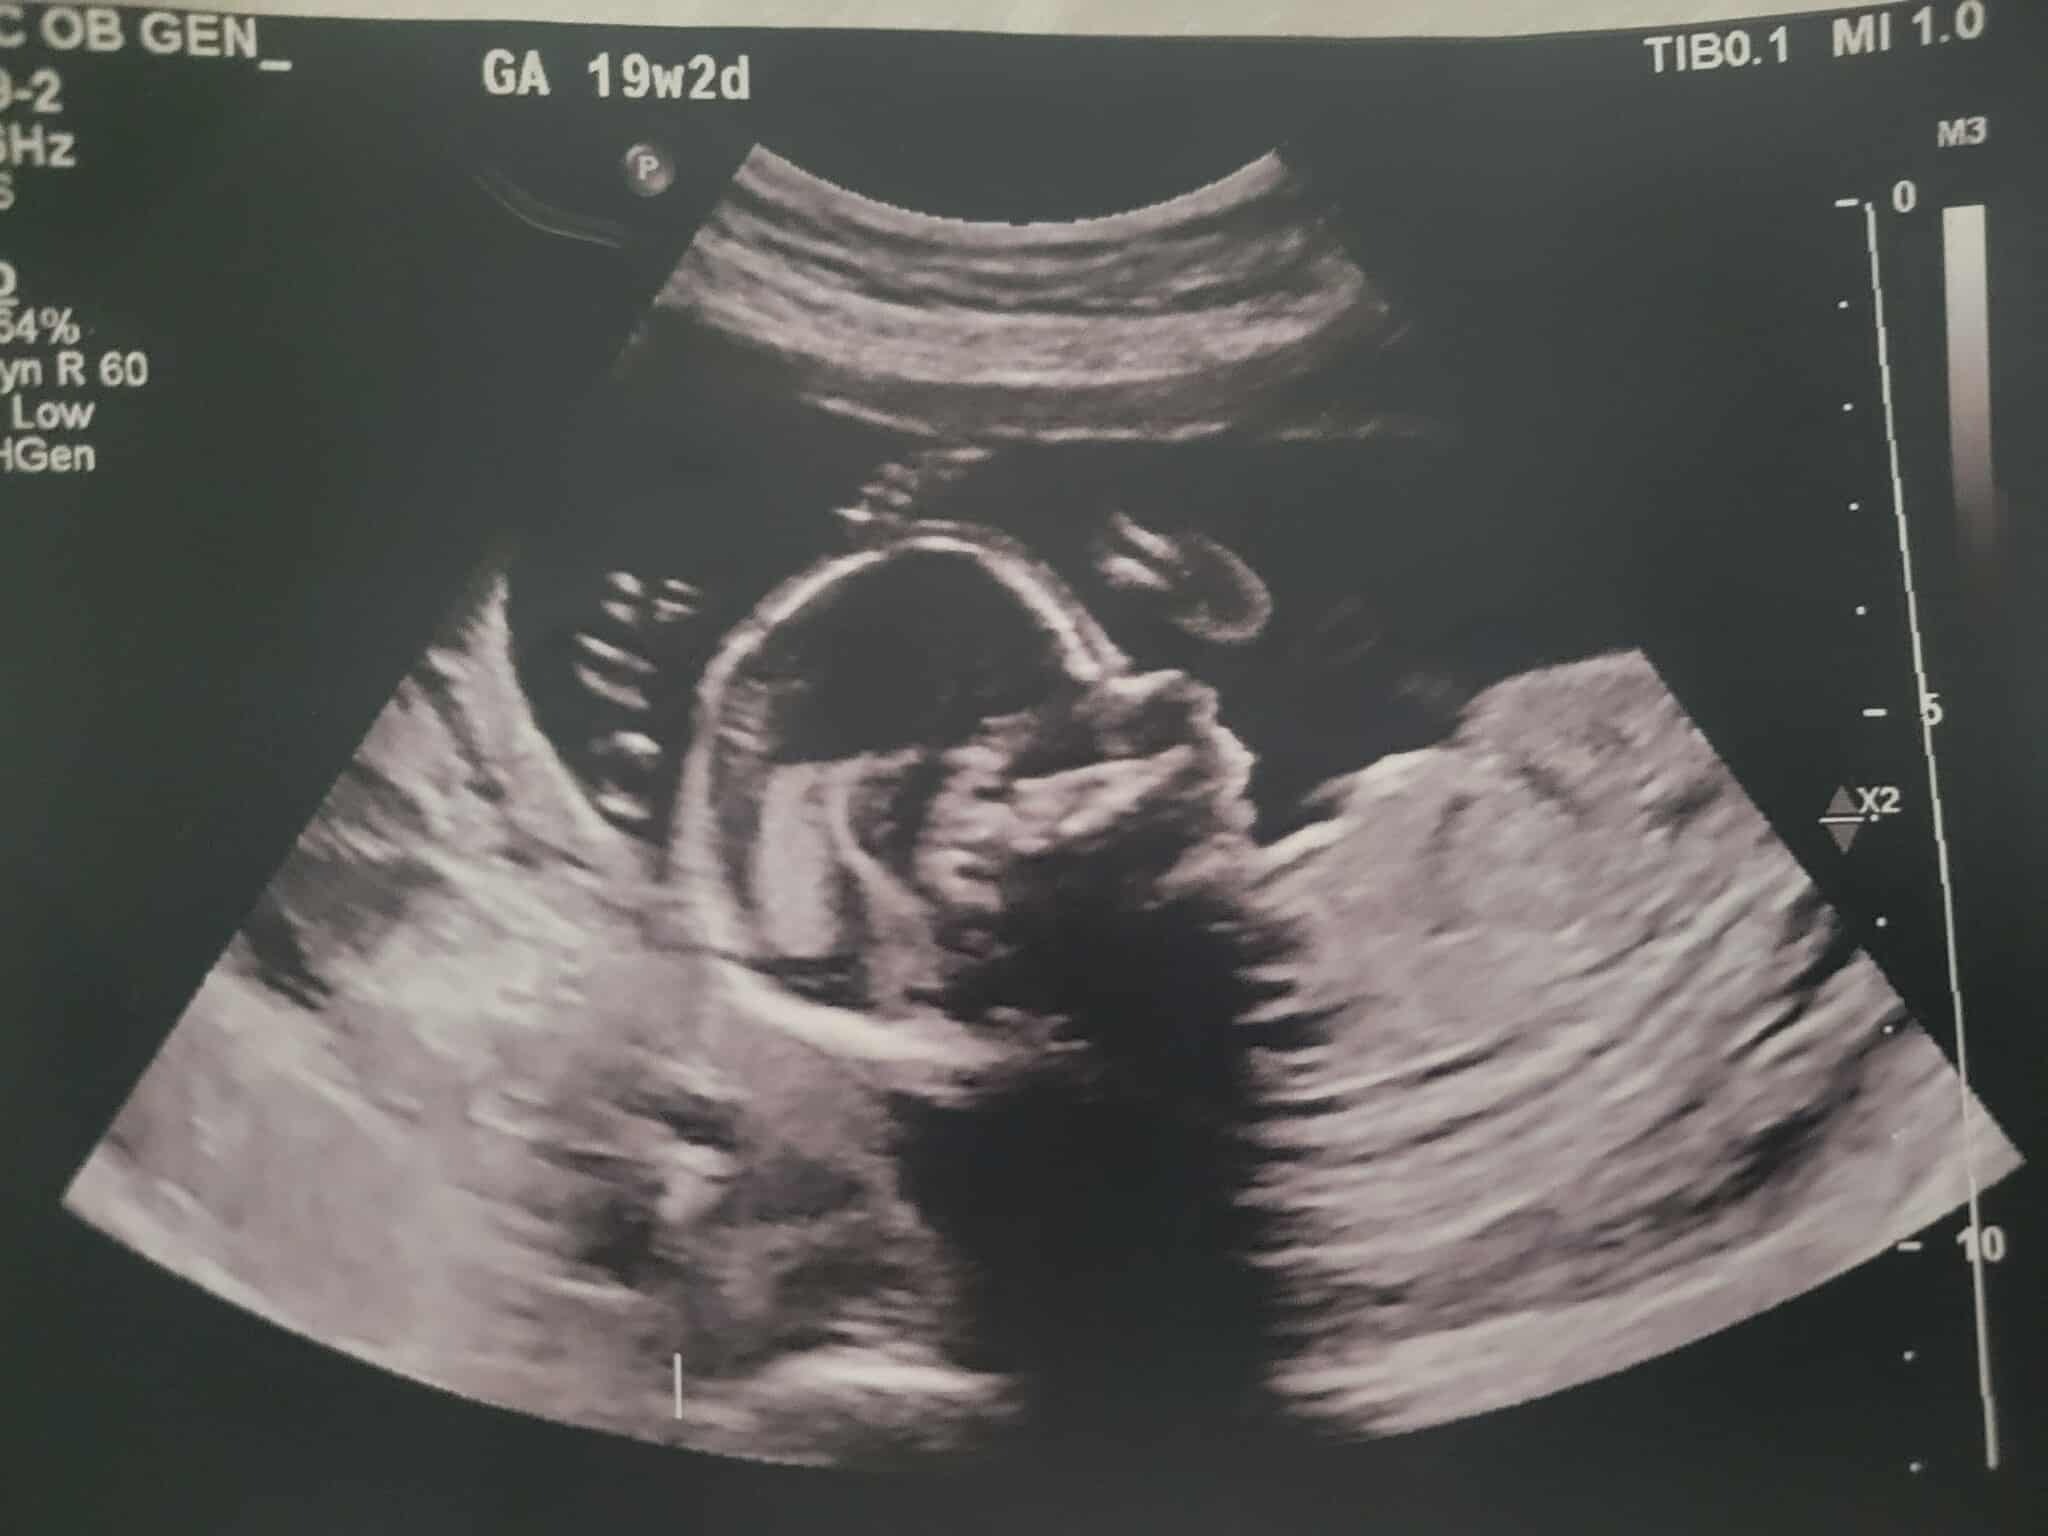

Hello, our names are Colleen and Jonathan King. We are reaching out for help with the journey of our baby girl, Oliviah. What began with the excitement of expecting another blessing from the Lord, with the silly gender mishap (as some of you know), and cute little outfits and bows, has turned to feelings of heartbrokenness, powerlessness, and shattered disbelief. Yet, through all of this, we remain hopeful, knowing that God has a hand in all of it. Following my 19-week ultrasound, we received the devastating news that Oliviah has been diagnosed with a L4 Myelomeningocele, a form of spina bifida. In Oliviah's case, the defect is low on her back, at the lumbar region, which is a good thing. She also shows the "banana and lemon signs," which is due to an elongated cerebellum, which is a sign of the Chiari II malformation, which means her brainstem is being pulled down into her spinal canal at the C2-C3 region. Her head circumference is also below percentile, caused by the Chiari II malformation.